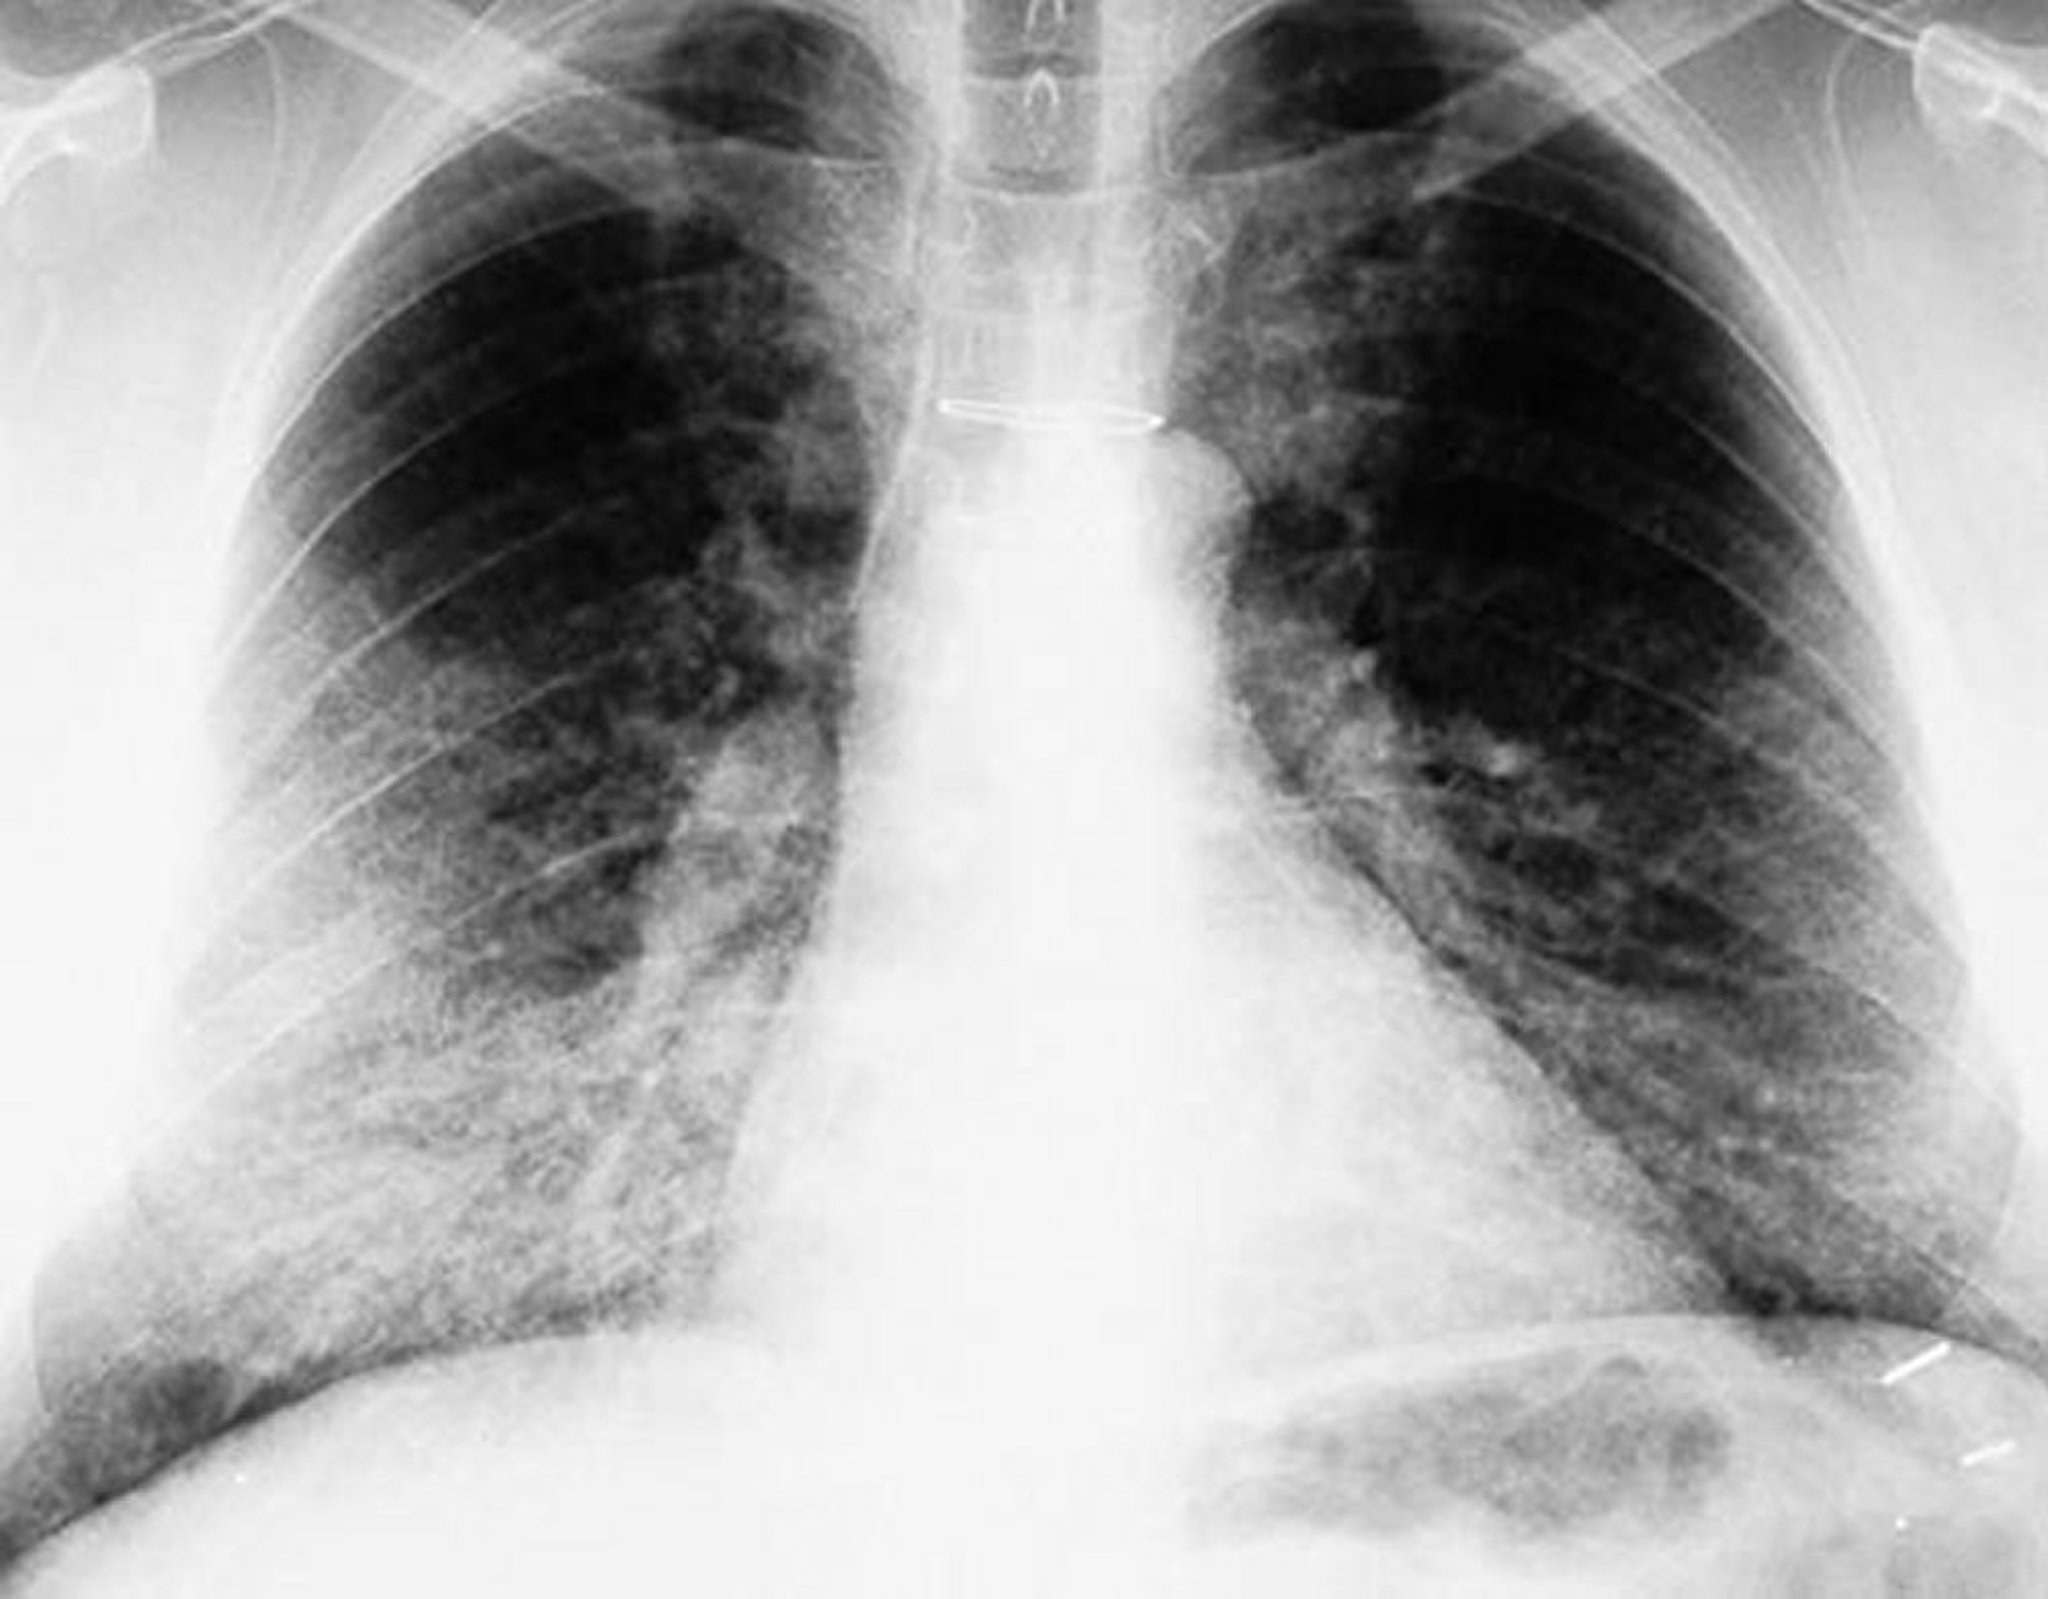

Proteinosis alveolar pulmonar (radiografía de tórax)

La radiografía de tórax muestra opacidades bilaterales, principalmente basales.

By permission of the publisher. De Lynch III J, Myers J. In Bone's Atlas of Pulmonary and Critical Care Medicine. Edited by J Crapo. Philadelphia, Current Medicine, 2005.